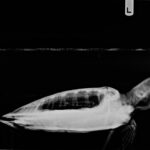

4.9 lb non-FP juvenile green, found in the tide line just north of county access 6 on SPI

minor abrasions on carapace/plastron from possible predator attack, minor abrasion on right eye